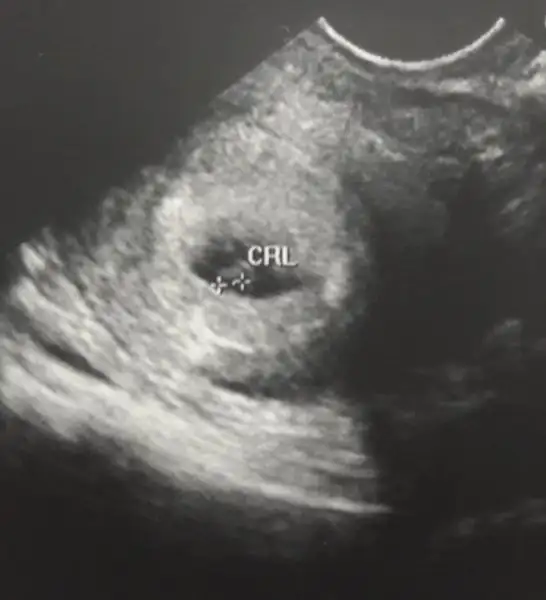

Kızlar merhaba bende akşm muayene oldum keseyi gördük haftaya cumartesi kalp atışlarını dinlemek için kendi doktorumdan randevu aldım inşallah rabbim onuda duymayı nasip eder